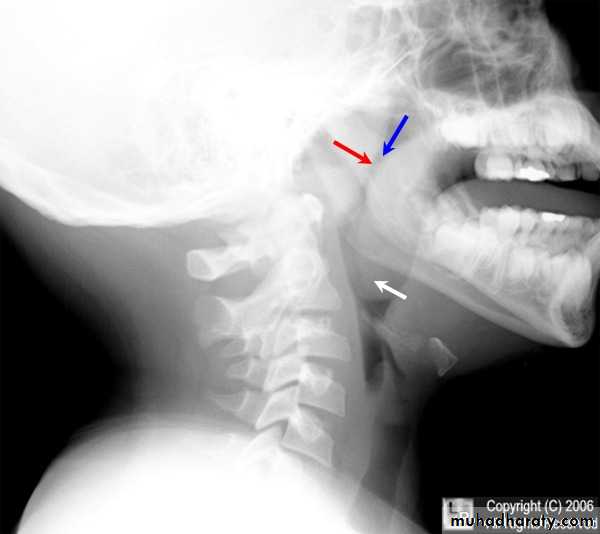

Lateral plain x-ray of the nasopharynx: A soft tissue shadow narrowing the airway => diagnostic.